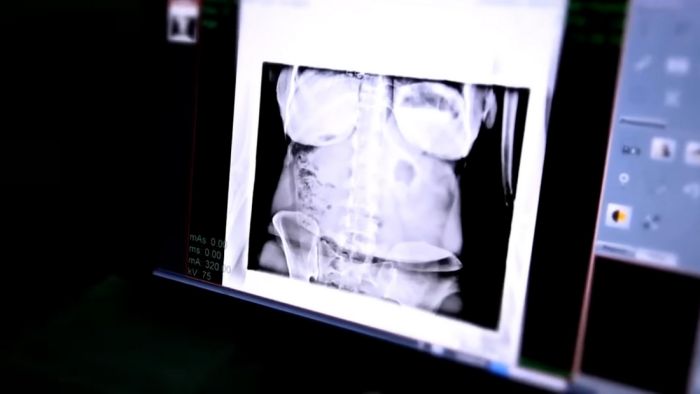

При этом женщина совершенно здорова. Она утверждает, что обращалась к врачам в Аддис-Абебе, чтобы узнать, что с ней. Медики проводили тесты на протяжении трех лет и пришли к выводу, что Амбав здорова физически. При этом они отметили, что в ее пищеварительном тракте нет ни еды, ни воды, ни продуктов жизнедеятельности. Амбав также утверждает, что обращалась к врачам из Катара и ОАЭ, чтобы проверить свое психическое состояние, и они не нашли никаких отклонений.